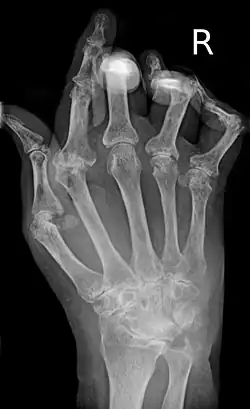

A hand severely affected by rheumatoid arthritis. This degree of swelling and deformation does not typically occur with current treatment. | |

As the pathology progresses, the inflammatory activity leads to tendon tethering and erosion and destruction of the joint surface, which impairs range of movement and leads to deformity. The fingers may develop almost any deformity depending on which joints are most involved. Specific deformities, which also occur in osteoarthritis, include ulnar deviation, boutonniere deformity (also "buttonhole deformity", flexion of proximal interphalangeal joint and extension of distal interphalangeal joint of the hand), swan neck deformity (hyperextension at proximal interphalangeal joint and flexion at distal interphalangeal joint) and "Z-thumb." "Z-thumb" or "Z-deformity" consists of hyperextension of the interphalangeal joint, fixed flexion, and subluxation of the metacarpophalangeal joint and gives a "Z" appearance to the thumb.[16]: 1098 The hammer toe deformity may be seen. In the worst case, joints are known as arthritis mutilans due to the mutilating nature of the deformities.[20]